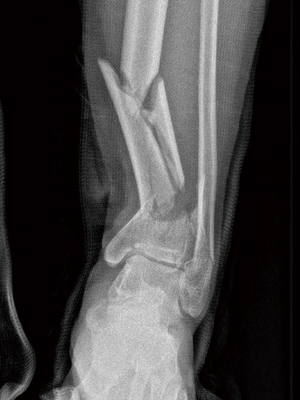

발 · ​발목골절당일수술(금식 8시간) Ankle Fracture

발목 골절이라고 다 같은 것이 아니기 때문에 상태에 맞는 치료가 필요합니다.   골절의 정도가 심하지 않은 경우에는 깁스로 고정을 하여 자연 유합을 시킬 수 있습니다.   골절 정도가 심한 경우에는 발목골절수술을 진행할 수 있습니다.

골절 당일수술은 8시간 금식 후 내원 시 바로 수술 가능합니다. *물 & 커피 포함 일체 금식 및 금연*​

발목 골절은 기존의 골절 부위를 잘 맞추고 고정하는 것이 매우 중요합니다.  특히 관절면을 잘 맞추는 것이 중요합니다.

골절된 발목​

관혈적 정복술 및 내고정 수술​

수술 후 유합된 발목​

X-ray

X선을 이용하여 조영제가 기구 등을 사용하지 않고 인체를 촬영하는 것입니다. 방사선을 인체에 투과하여 나타는 음영의 차이를 이용해 진단하는 검사로 뼈를 진단할 수 있습니다.